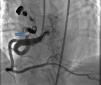

Case reportA 49-year-old woman was admitted to our outpatient clinic with complaints of exertional dyspnea, exertional chest pain, paroxysmal palpitation attacks, and fatigue. She had been treated for diabetes for two years but had no additional risk factors for coronary artery disease. On physical examination, her blood pressure was 130/80 mmHg and heart rate 85 bpm. No pathological sounds were heard during pulmonary and cardiac auscultation. Routine biochemical and hemogram values were within normal ranges. Ejection fraction was 60%, and no serious valve disease was detected on transthoracic echocardiography. Electrocardiography showed sinus rhythm. Right atrial tachycardia was induced with programmed atrial stimulation during a diagnostic electrophysiologic study (Figure 1). Coronary angiography was also performed in order to clarify potential ischemic etiology. While the left coronary and right coronary arteries were found to be normal, a giant fistula was detected from the proximal portion of the right coronary artery to the right atrium (Figure 2). Qp/Qs was 1:1 by oximetry and all right heart pressures were within normal ranges during right heart catheterization. Computed tomography (CT) angiography was also conducted for a detailed anatomical assessment, which showed a fistulized artery about 8 mm in diameter originating from the right coronary artery 2 cm distal to the orifice and draining into the intersection of the inferior vena cava and right atrium after following a tortuous course (Figure 3). The patient's symptoms were considered to be related to a coronary steal phenomenon in addition to the arteriovenous shunt caused by such a large fistula. A percutaneous occlusion procedure was preferred for the patient's comfort and to avoid complications likely to be caused by surgery. During the procedure, a Judkins guiding catheter was placed in the right coronary artery ostium and the fistulized artery was selectively catheterized via microcatheter, then multiple coils with different sizes ranging from 9 mm to 3 mm were sequentially placed in a suitable location in the mid portion of the fistulized artery until total occlusion was achieved (Figure 4). The patient's atrial tachycardia could not be induced again during the control electrophysiologic study repeated at the end of one month. Finally, progressive improvement was observed in exertional capacity, and other symptoms including paroxysmal palpitations completely disappeared during follow-up.

Congenital CAF is defined as the presence of a direct communication between a coronary artery and any cardiac chamber or vessel.1 Although rare, they are the most common hemodynamically significant congenital coronary artery anomaly.1,2 Fistulized arteries may be open to either the systemic or the pulmonary circulation. They may be congenital or acquired. The pathophysiological mechanism in congenital CAF is described as continuance of the sinusoidal connections which maintain myocardial blood flow in the early embryological period. Acquired CAF may be caused by cardiac trauma, surgery, percutaneous intervention or pacemaker installation, or be secondary to inflammation.3 In their series of 126595 cases of patients undergoing coronary angiography, Yamanaka and Hobbs reported an incidence of coronary artery anomalies of 1.3%, while that of CAF was 0.18% (13% of all coronary artery anomalies).4 Fistulized arteries, originating in the right coronary artery or its branches, comprise 50–55% of all CAFS. In terms of the structures with which coronary fistulas are connected, 40% are fistulized to the right ventricle, 25% to the right atrium, 15–20% to the pulmonary artery, and 7% to the coronary sinus.5 In our case, a giant fistula was detected originating in the proximal right coronary artery and draining into the intersection of the inferior vena cava and the right atrium.